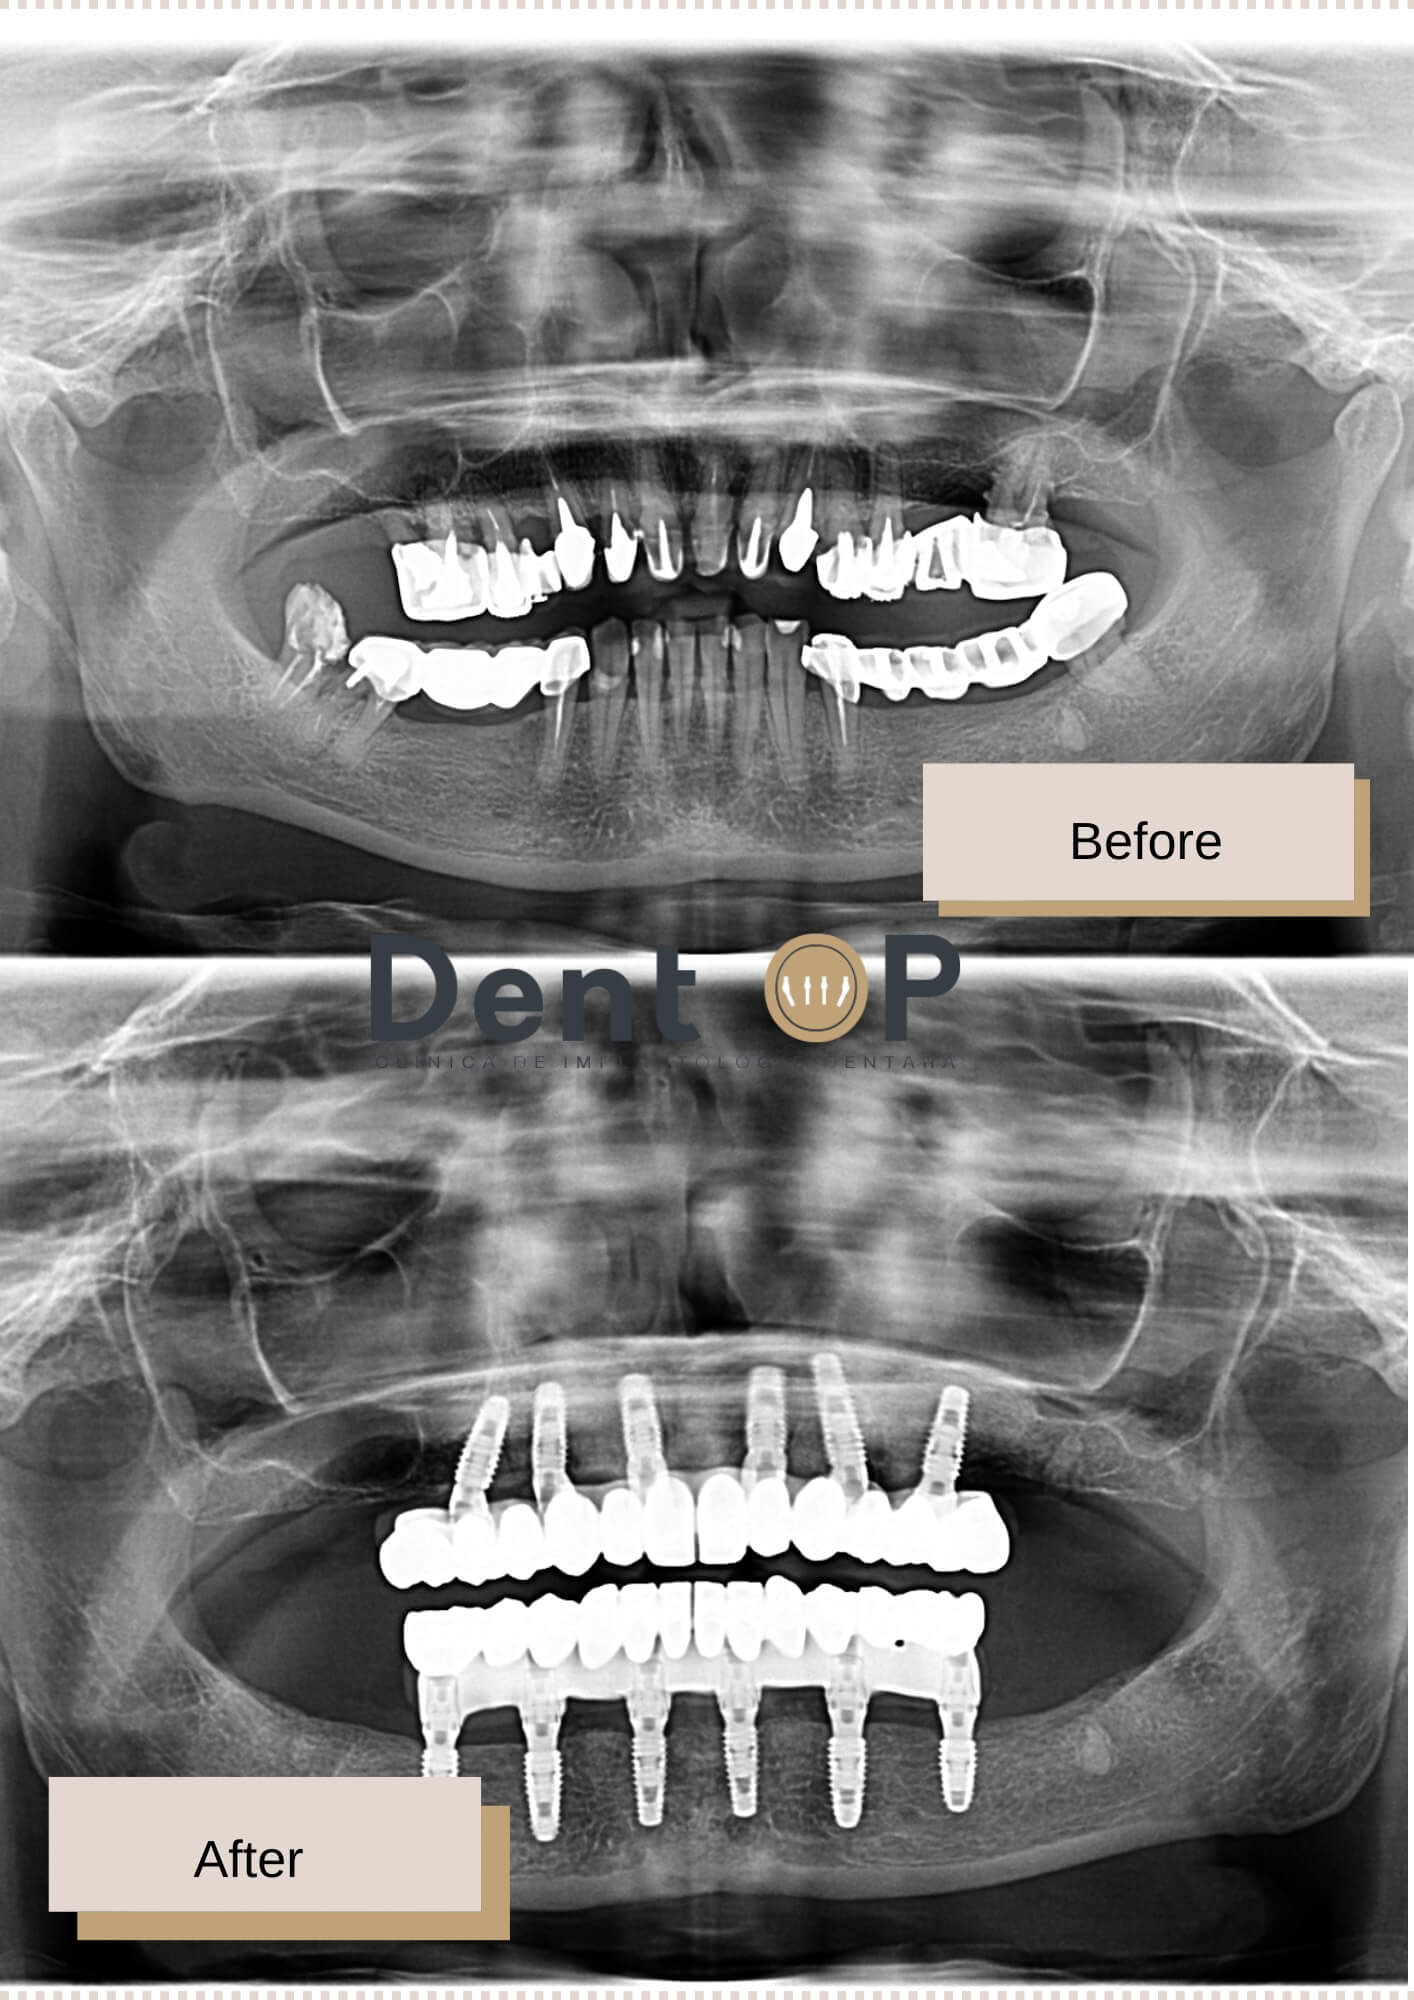

A avut boala parodontală, carii severe și lucrări vechi instabile. Doamna A. a trebuit să renunțe la toată dantura.

S-a prezentat în cadrul clinicii cu foarte multe probleme dentare. De la boala parodontală la carii severe și lucrări vechi. Dantura nu i-a putut fi salvată, motiv pentru care a luat în calcul soluția cu implanturi dentare.

A urmat apoi să-i fie inserate cele 12 implanturi dentare + lucrarea provizorie chiar din a doua zi. Doamna A. s-a prezentat la controale periodice și astfel am putut ține sub control situația sa dentară. După 4-6 luni, i-a fost inserată și lucrarea finală, care i se potrivește de minune.